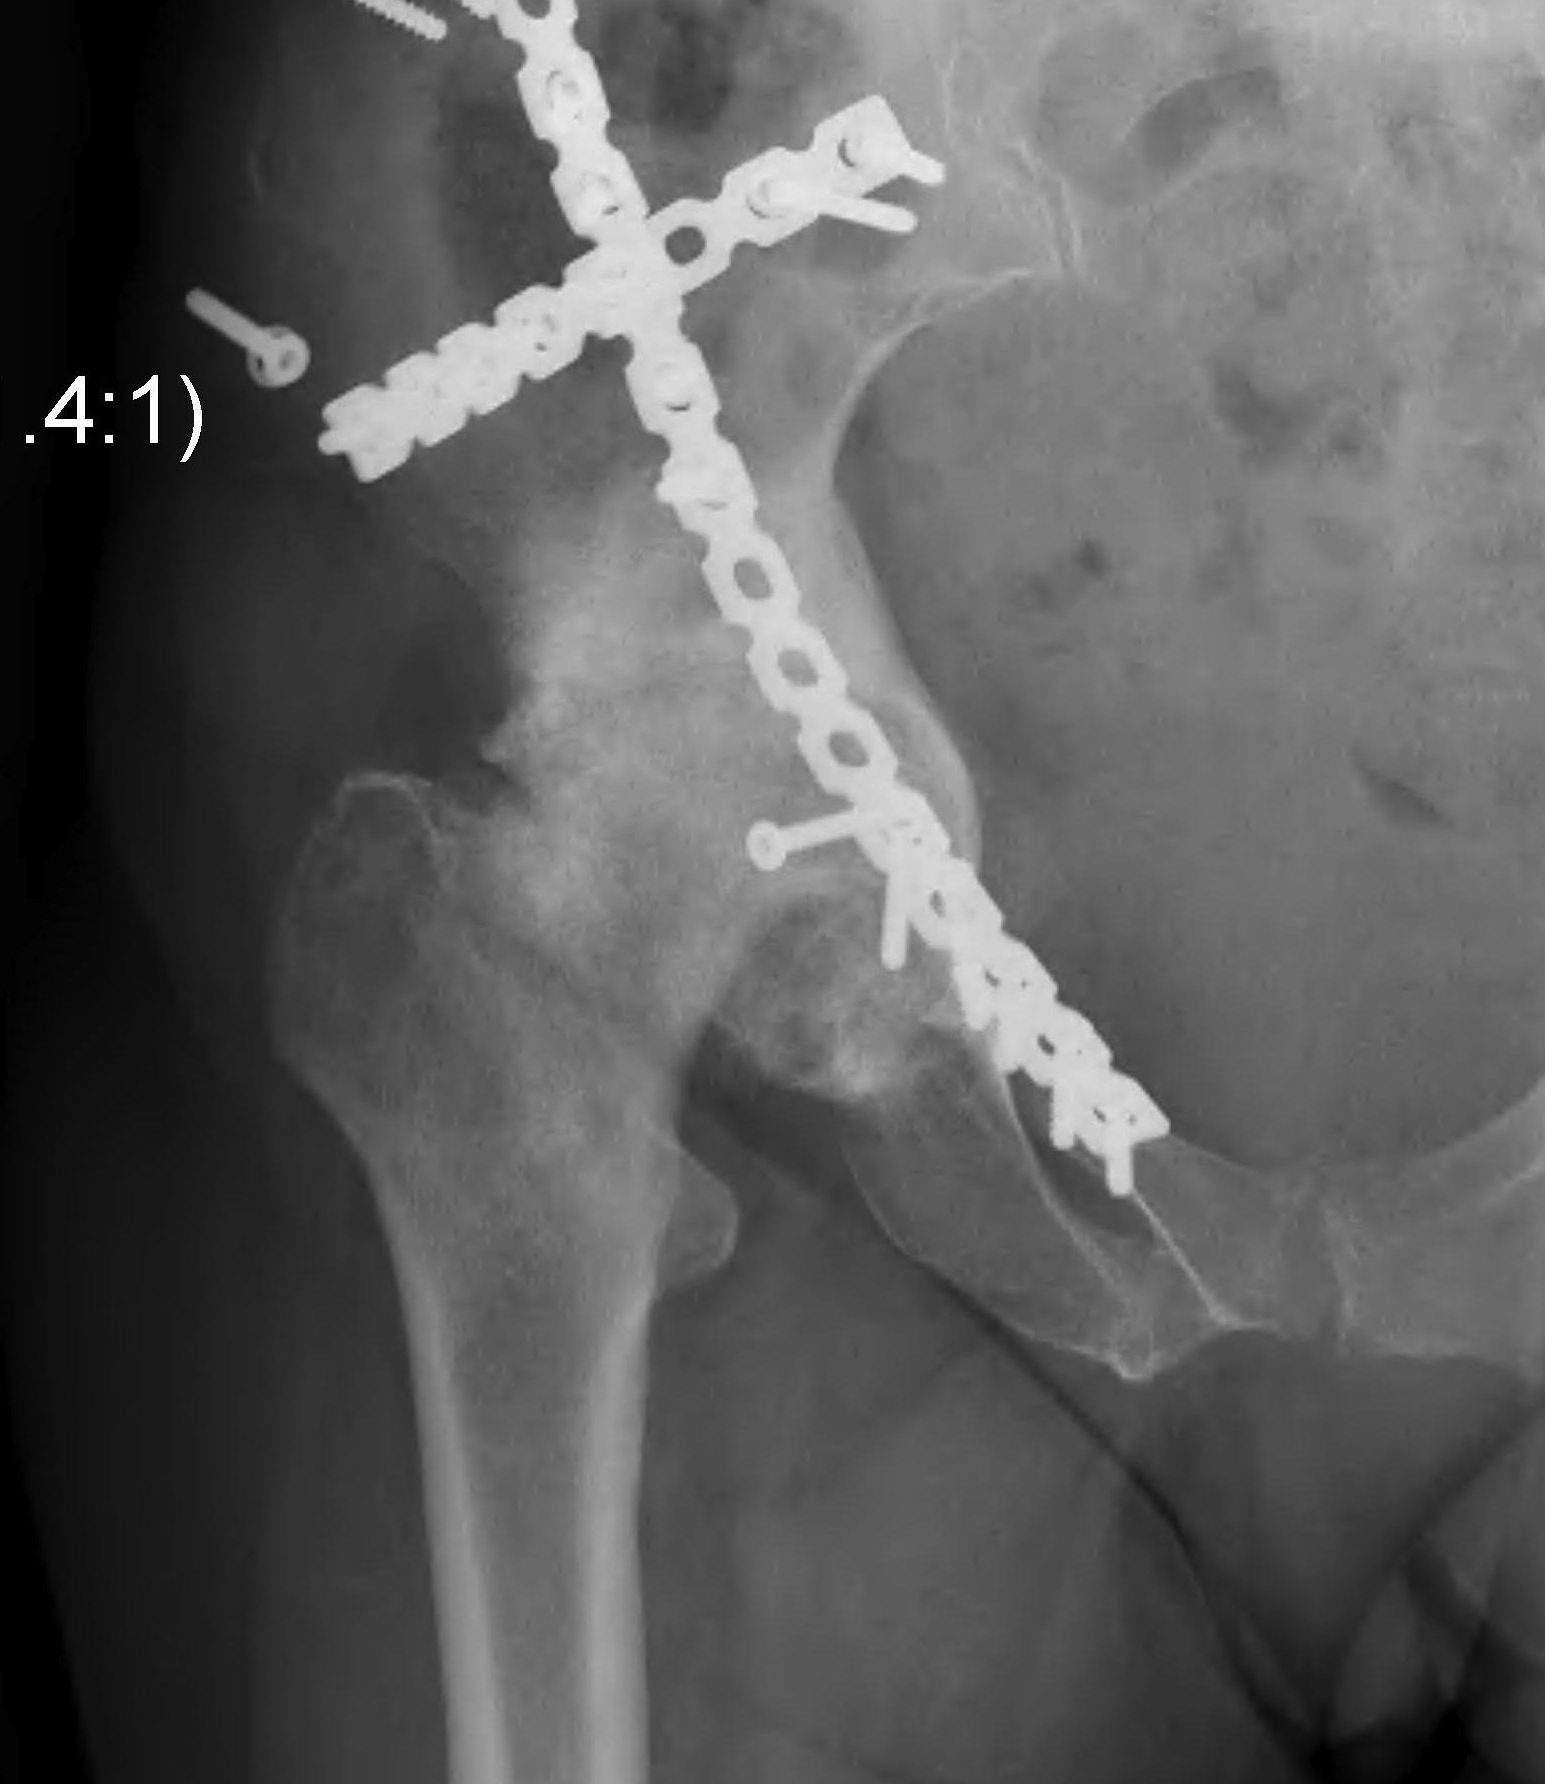

Trauma